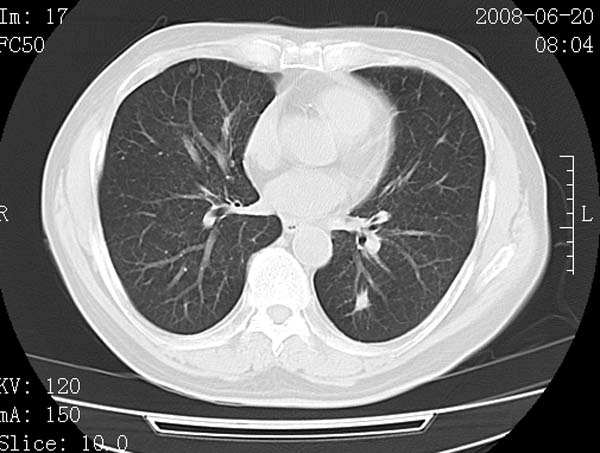

以下是引用守望可可西里在2008-6-24 1:11:00的发言:[br][br] 考虑为周围型肺癌:[br] 1.分叶结节,形态极不规则,蟹足样伸展的恶性浸润特征比较明确。[br] 2.磨玻璃影中由多个更高密度小结节聚集呈梅花瓣样。[br] 3.局部胸膜凹陷征比较明确。[br][br] 另:纵隔胸膜明显增厚、粘连。

以下是引用zjzjr在2008-6-24 11:19:00的发言:[br]支持左下肺周围型肺癌伴右肺转移,纵隔淋巴结转移,心包积液.

以下是引用zhangling在2008-6-24 14:56:00的发言:[br]我们科室意见报告为[br][br]1考虑左下肺周围型肺癌[br]2右肺小结节考虑转移瘤,纵隔淋巴结转移[br]3心包积液. [br] 各位老师分析的相当好 谢意[br]